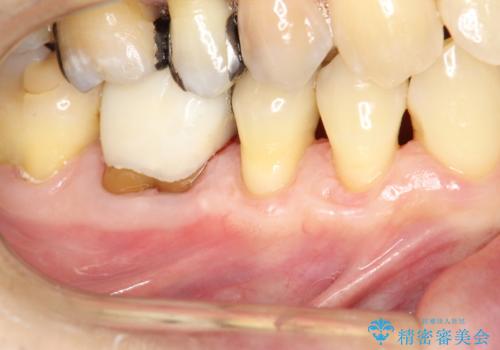

徐々に下がってきた歯肉へ再生療法(歯冠側移動術と結合組織移植術の併用)を施術し、丈夫な歯肉を獲得させた症例

担当医 林佳士登